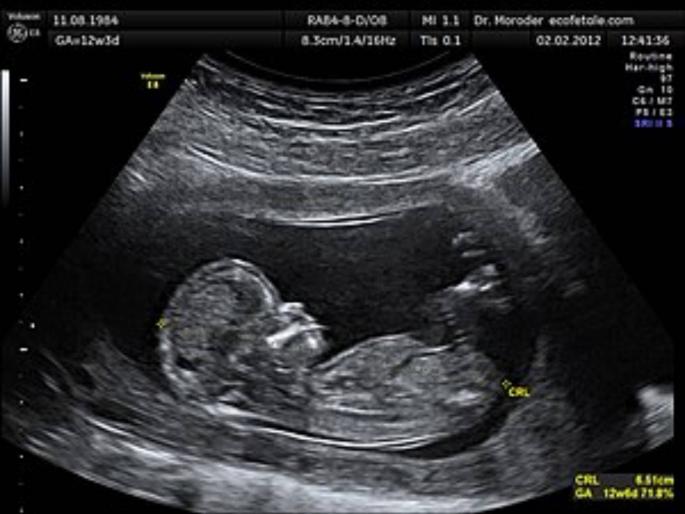

सोमनाथ खताळ, लोकमत न्यूज नेटवर्क, बीड: गेवराईतील गर्भलिंग निदान प्रकरणातील रेट कार्ड समोर आले आहे. यामध्ये एका तपासणीला २५ ते ४० हजार रुपये घेतले जात होते. डमी रुग्णाकडूनही ३० हजार रुपये घेतले. यातील ५ हजार रुपये घरमालक चंद्रकांत चंदनशिव, ११ हजार रुपये डॉ. सतीश गवारे, तर राहिलेले १४ हजार रुपये मनीषा सानप स्वत:कडे ठेवत होती, असे सूत्रांनी सांगितले. पोलिसांनी मनीषाचे वर्षभराचे कॉल डिटेल्स मागविले आहेत. त्यातून संपर्कात कोण कोण हाेते, हे समजणार आहे. गर्भलिंग प्रकरणाचा ५ जानेवारीला पोलिस, आरोग्य विभागाने कारवाई करून पर्दाफाश केला होता.